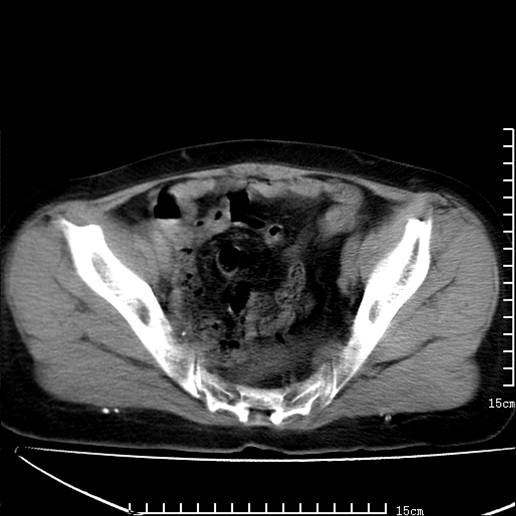

以下是引用pujunzhi在2008-5-30 15:31:00的发言:[br]异位肾—盆腔肾。当看到肾窝无肾脏时,要想到孤立肾和异位肾,异位肾最常见是盆腔肾,偶见胸腔,易误认为肺占位,只要想到就不会漏诊。建议增强扫描。